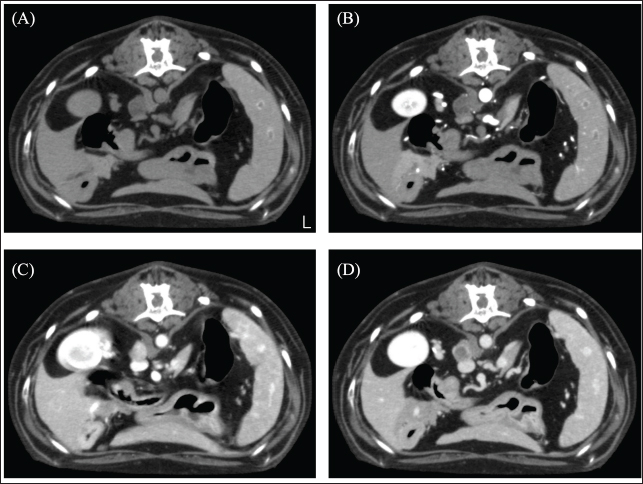

A 12-year-old spayed female French bulldog weighing 12.2 kg was visited by a veterinarian for a medical checkup. The dog had no clinical symptoms and was in good general condition; however, chest radiography revealed a mass in the left thoracic region. The dog was referred to the Okayama University of Science Veterinary Medical Teaching Hospital for close examination and treatments (day 1). The dog’s temperature was 38.3°C, heart rate was 100 beats/minute, and respiratory rate was 40 beats/minute. The non-obstructive blood pressure was as follows: systolic arterial blood pressure (SAP), 168 mmHg; mean arterial blood pressure (MAP), 124 mmHg; and diastolic arterial blood pressure (DAP), 119 mmHg. No abnormal values were observed in complete blood counts. Blood chemistry tests showed mild hypercholesterolemia (474 mg/dl), mild elevation of alkaline phosphatase (ALP; 629 U/l), and alanine aminotransferase (86 U/l) levels, and a mild decrease in blood urea nitrogen (7.5 mg/dl). The dog presented with polyurea or polydipsia. In the ACTH stimulation test, the postcortisol level was 27.8 µg/dl. Therefore, it was determined that the case presented with Cushing's syndrome as an underlying disease. Computed tomography (CT) scan (Aquilion Lightning; Canon Medical Systems Co., Otawara, Japan) performed in general anesthesia. Iopamidol (Oypalomin 300, Fuji Pharma, Japan) was used as a contrast medium [injection volume; 2.5 ml/kg (750 mgI/kg), injection time; 15 seconds]. Precontrast (before the injection of contrast medium), arterial phase (15 seconds after the start of injection), venous phase (40 seconds after the start of injection), the equilibrium phase (120 seconds after the start of injection) scans were obtained. The mass (42 × 39 × 44 mm) showed in the basilar left caudal lobe. The mass was in contact with the left cranial lobe, was strongly contrast-enhanced in the venous phase, and rapidly washed out in the equilibrium phase (Fig. 1). The right middle tracheobronchial lymph nodes were enlarged and showed a contrast-enhancement pattern similar to that of the mass in the left caudal lobe (Fig. 2). An incidentally enlarged right adrenal gland is also observed. The right adrenal gland was enlarged to 10 mm, spherical with a smooth limbus, contrast-enhanced at the limbus, peaked in the venous phase, and was attenuated in the equilibrium phase (Fig. 3). Based on the CT findings, we tentatively diagnosed the patient with a primary lung neuroendocrine tumor with lymph node metastasis. The anesthesia was stable during the CT scan, and no significant blood pressure fluctuations were observed.

Fig. 3. CT image of the abdomen. (A) Plain, (B) arterial phase, (C) venous phase, and (D) equilibrium phase. The right adrenal gland was spherical with a smooth limbus, contrast-enhanced at the limbus, peaked in the venous phase, and attenuated in the equilibrium phase. The mean CT values of adrenal tumors were 22.23 HU in arterial phase, 87.58 HU in venous phase, and 48.21 HU in equilibrium phase.

In this case, CT showed a left caudal lobar mass, enlarged middle tracheobronchial lymph nodes, and a right adrenal mass. The pulmonary mass was strongly enhanced in the venous phase and was washed out in the equilibrium phase. A previous study reporting the CT findings of paragangliomas in 10 dogs showed strong contrast enhancement in the arterial and venous phases (Gombert et al., 2022). The strong contrast-enhancing effect and subsequent washout of the left caudal lobar mass seen in this case are characteristic imaging findings that are suspicious for neuroendocrine tumors and are also seen in insulinomas and carcinoids, in addition to paragangliomas (Fukushima et al., 2016; Kutara et al., 2017). The resected lung mass was diagnosed as a neuroendocrine carcinoma by pathological examination, which was consistent with the imaging findings. In short, even in paragangliomas of the lung, this characteristic contrasting finding may help in decision-making. The enlarged right tracheobronchial lymph node showed the same contrast pattern as the mass and was suspected to be metastatic. Although pathological evaluation of the right adrenal mass was not performed in this case because it was not removed, it has been reported that adrenal masses can be diagnosed preoperatively using a triple-phase helical CT scan (Yoshida et al., 2016). In this case, the right adrenal mass was 10 mm in size with a smooth limbus and contrast enhancement at the limbus, peaking in the venous phase and diminishing in the equilibrium phase. Following previous reports, the right adrenal mass was considered an adrenal adenoma rather than a suspected pheochromocytoma. In this case, blood tests revealed elevated ALP levels, possibly due to the corticosteroids. Thus, based on these results, it was unlikely that the left lung mass was a metastatic lesion of the right adrenal mass and was considered a primary lung mass.